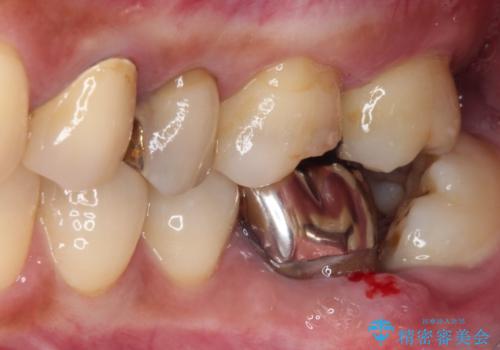

- 奥歯を治療しようと他院で開始したものの、放置してしまったとのことで来院された患者様です。

外れてしまった銀歯や穴の空いた仮歯などあり、適合の悪い被せものと合わせて、セラミッククラウンやセラミックインレーにて治療と行うこととしました。